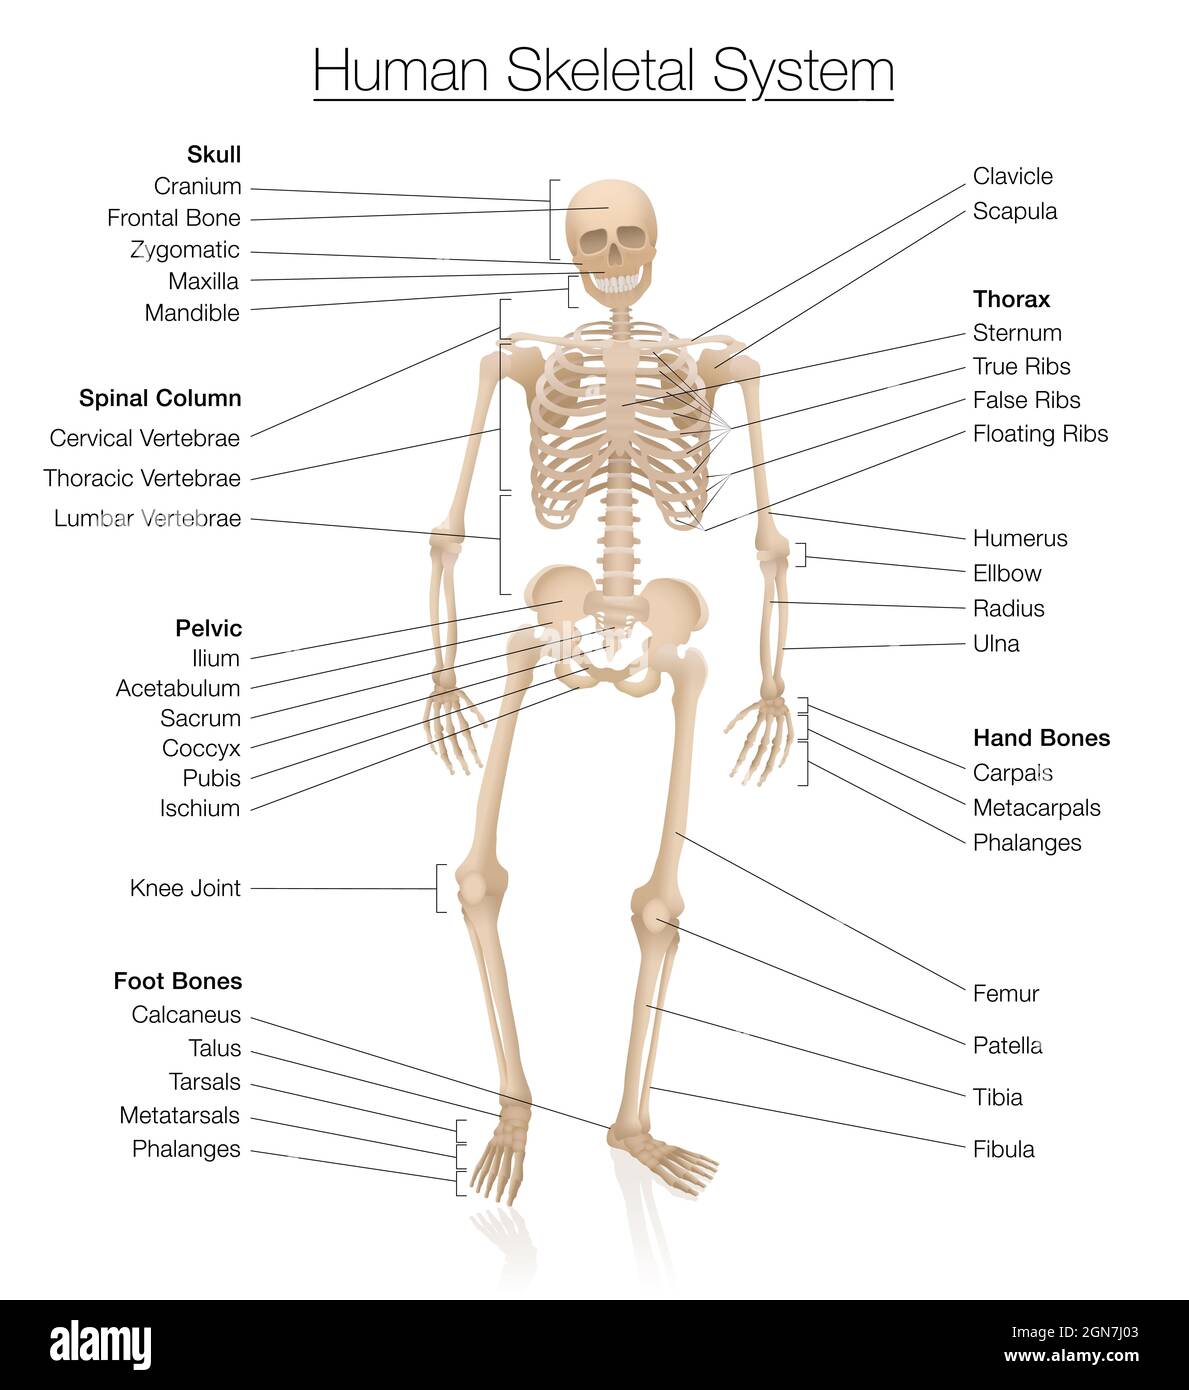

RF2GNRHN3–Anatomie du squelette - carte du système squelettique humain - marquée avec les os les plus importants comme le crâne, la colonne vertébrale, le bassin, le thorax, les côtes, sternum, main.

RF2H0KT2F–Diagramme squelette humain.Système squelettique marqué avec os nommés, crâne, colonne vertébrale, bassin, thorax,côtes, sternum, os des mains et des pieds, clavicule.